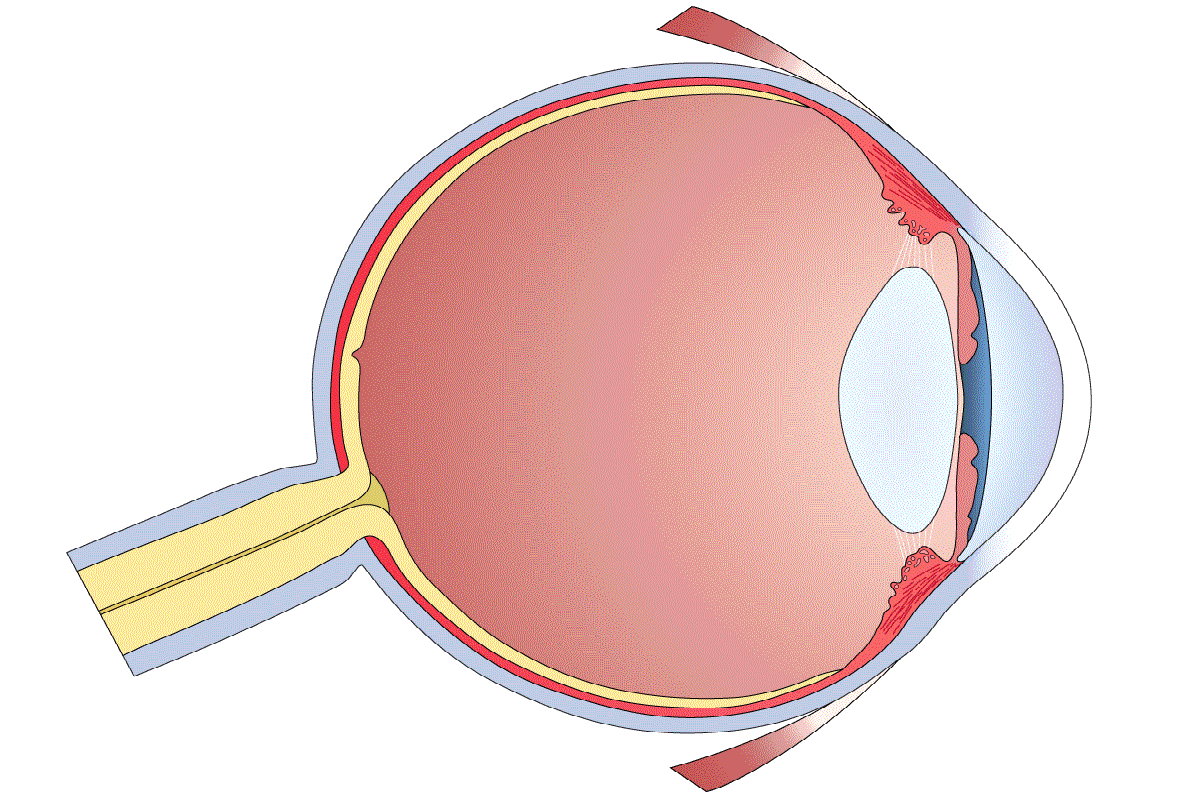

КТ-графики и изображение строения глаза